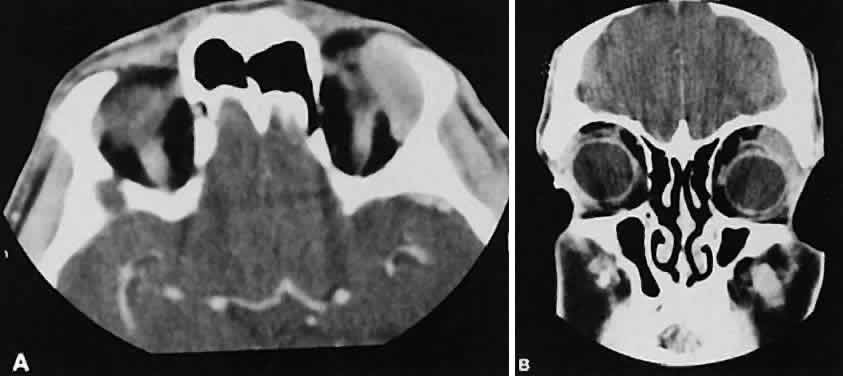

Optimal visualization of the orbit requires imaging from at least two planes. Axial slices should be oriented parallel to the optic nerve (-10 degreesto the orbitomeatal line) and no thicker than 3 mm. Axial views, because of volume averaging, may miss lesions located along the floor or roof. Additional views, typically coronal, can be obtained by reformatting data obtained during axial imaging or by direct coronal scanning.

Direct coronal views usually are preferable because of better resolution.6,7 They can be obtained by having patients lie either prone or supine, extending their neck, and angulating the gantry sufficiently to provide coronal imaging while avoiding artifacts from the teeth. Direct coronal scans also should be no thicker than 3 mm.

Coronal views may need to be reformatted from axial scans if a patient has extensive dental fillings, is anesthetized, or cannot extend the neck sufficiently for direct coronal scanning. The resolution on these images can be improved if data are collected from 1.5-mm contiguous axial slides.6 Spiral CT has resulted in improved multiplanar reformation with thin section (1 to 1.5 mm) axial images. High-resolution images necessary for leukocoria or foreign body imaging are obtained with 1-mm axial slices at 1:1 pitch at 1-mm intervals. Ideally, most screening orbit studies are performed at 3-mm direct axial and direct coronal images.

An appreciation for the various pathologic processes that affect the orbit is facilitated by an understanding of the normal orbital anatomy (Fig. 1). The orbit is a pyramid-shaped bony structure bounded inferiorly by the maxillary sinus, medially by the ethmoidal sinus, and superiorly by the frontal sinus. The sphenoidal sinus is situated posteriorly along the medial orbital wall and has a common wall with the optic canal. The lacrimal gland lies within its fossa located in the superior temporal aspect of the orbit and can be seen on both axial and coronal views.

The extraocular muscles (EOMs), with the exception of the inferior oblique, originate from the anulus of Zinn in the orbital apex. The inferior oblique takes its origin from the frontal process of the maxilla and is seen occasionally on CT imaging. The superior oblique, after originating from the anulus, courses along the superior nasal orbital wall just above the medial rectus muscle before passing through the trochlea. The rectus muscles conveniently form a muscle cone, which is sometimes helpful in terms of differential diagnosis. Before thinner axial slices and multiplanar imaging were available, an enlarged inferior rectus muscle often was imaged as an apical mass, especially if dysthy-roid optic neuropathy was present. The importance of imaging from two different planes cannot be overemphasized in this situation.

The optic nerve occupies the central intraconal space. By necessity, the nerve has a certain amount of slack, which is necessary to permit movement of the globe. In the axial plane, the optic nerve has an undulating course and thus may appear thicker or thinner as a result of partial volume averaging as it passes in and out of the axial plane. It is imperative to recognize this normal pattern for proper interpretation of axial images.